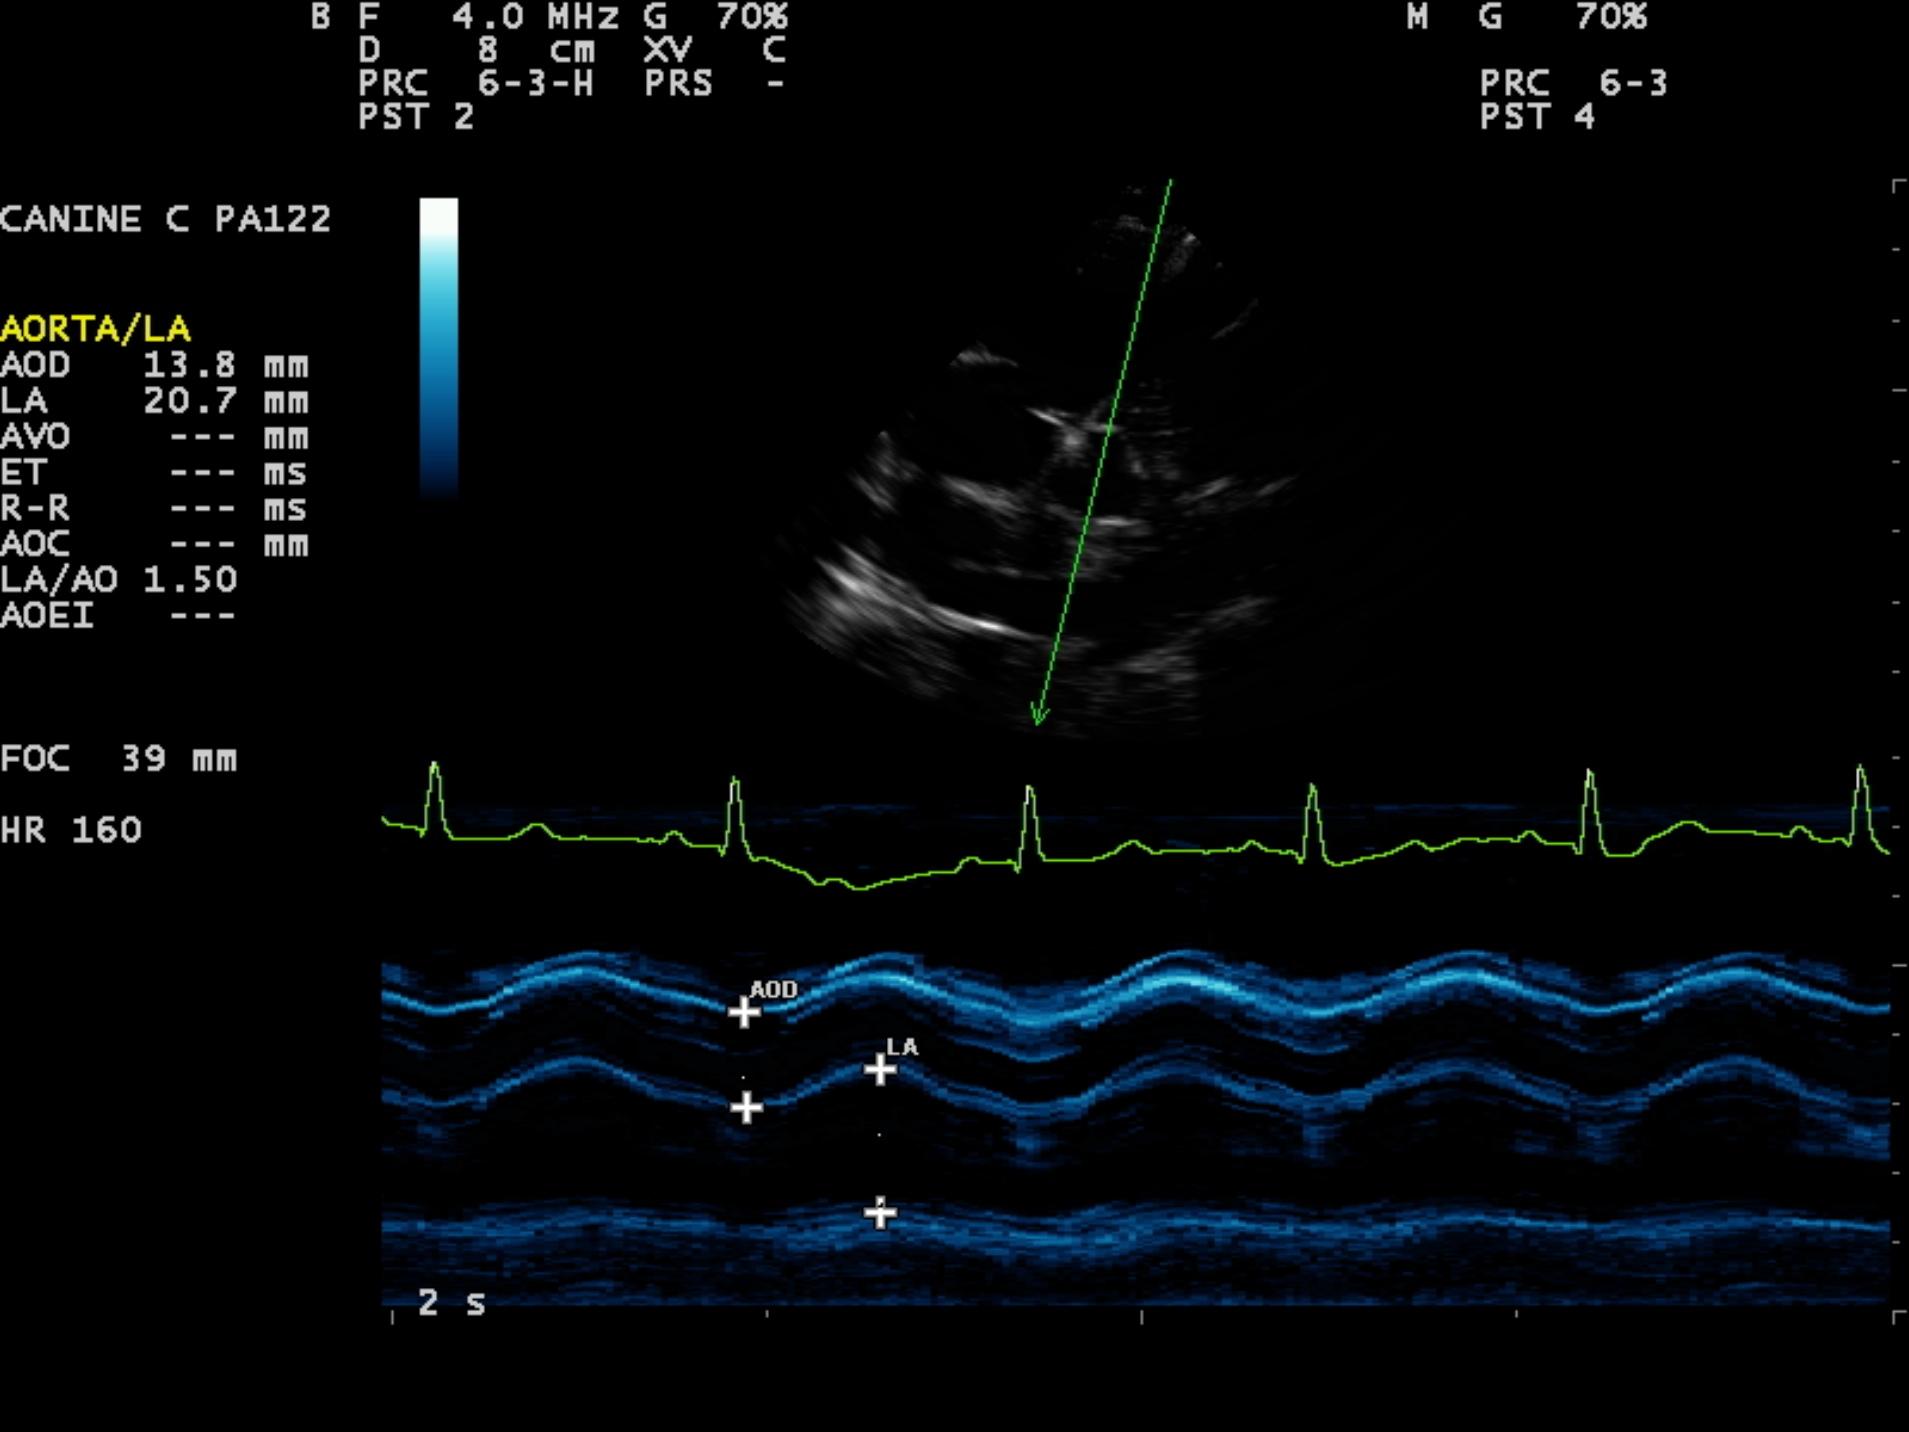

An 8-year-old F Maltese was presented for examination. A grade 5/6 systolic heart murmur was noted. Radiographs revealed severe generalized cardiomegaly and an unremarkable pulmonary parenchyma. Moderate hepatomegaly and ascites was additionally noted.